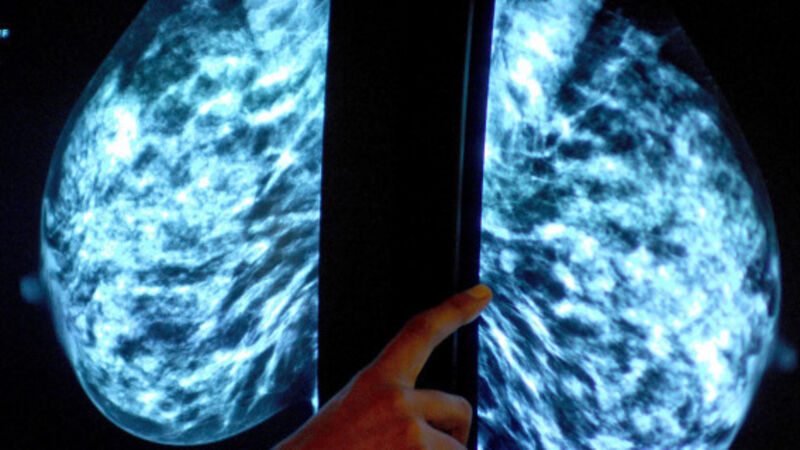

More people are surviving cancer in Ireland than ever before, the Irish Cancer Society has said.

The charity said that survival rates for the disease now stand at six in 10, compared with four in 10 in 1997.